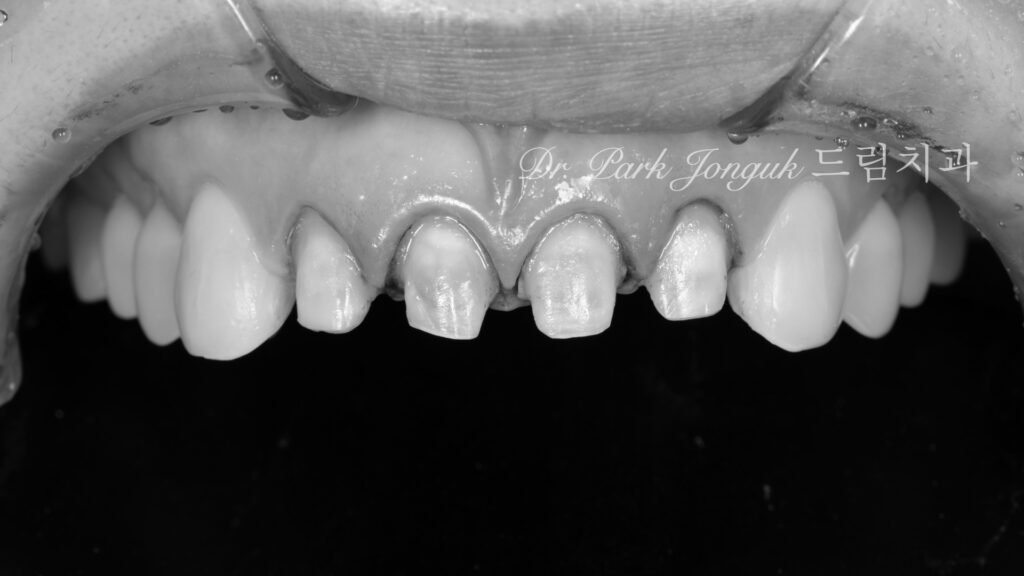

사진 6. 기존 크라운 제거 후

기존 보철물을 제거한 상태

과도하게 삭제된 치아가 드러났고, 일부는 신경 가까이 손상된 상태였습니다.

이런 경우, 재시술은 단순한 미용이 아니라 보존과 복원의 균형 작업이 됩니다.